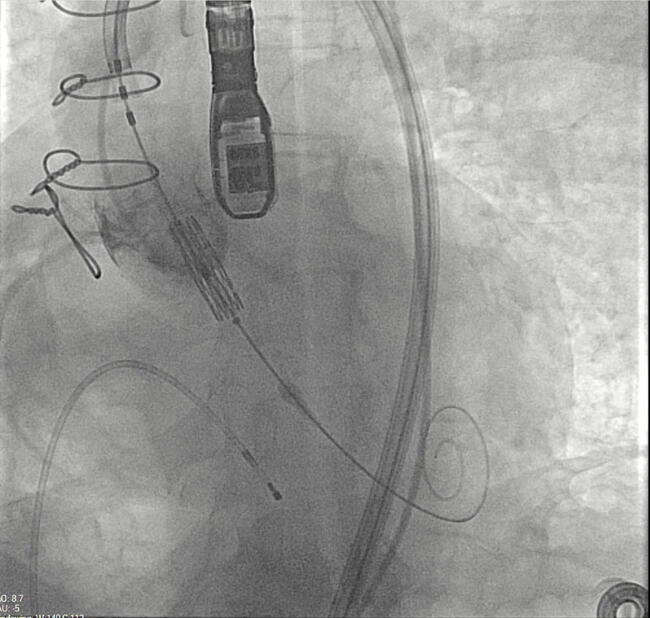

The use of stented bioprostheses facilitates THV deployment in ViV-TAVI, as most come with radiopaque markers that assist in precise placement. This benefit is diminished in stentless or homograft valves, where such markers are absent (Figure). Besides, there may be a lack of structural support for valve anchoring, particularly in cases of aortic regurgitation and no calcification.12 Data from the VIVD registry showed that stentless ViV-TAVI had a nearly doubled malposition rate and more than a double need for a second prosthesis compared with stented cases.9 Device oversizing may have played a role in malpositioning, especially given the lack of established sizing guidelines for failing stentless bioprostheses.

A balloon-expandable valve was used in 9 (60%) patients, while a self-expandable valve was deployed in the remaining 6 (40%) patients. Three high-risk patients for coronary obstruction underwent concomitant PCI with the snorkel technique to protect the coronary ostia. There were no cases of surgical conversion. However, 1 patient experienced THV malposition, requiring the deployment of a second valve; the THV migrated to the ascending aorta after post-dilatation and was snared to the ascending aorta to avoid further migration. A second THV was then placed across the previous stentless valve. During the postoperative period, this patient experienced a stroke and required the implantation of a new permanent pacemaker for a third-degree atrioventricular block. She was discharged and remains alive as of February 2025.